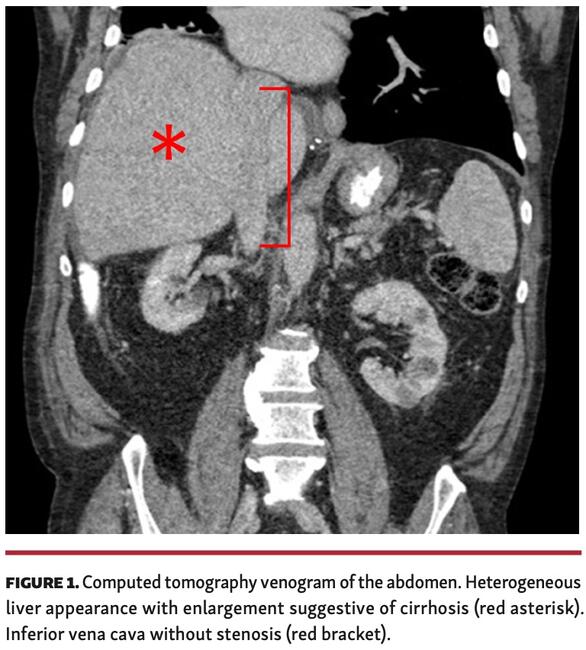

A 67-year-old man presented with new-onset abdominal pain, fullness, and lower-extremity edema approximately 2.5 years after bicaval orthotopic heart transplant from an appropriately sized donor. Cardiac allograft biventricular systolic function was normal and there was no histologic evidence of allograft rejection. Abdominal imaging revealed new findings of a nodular liver suggestive of cirrhosis, in addition to splenomegaly and ascites (Figure 1). There was no evidence of hepatic or portal vein thrombosis, nor stenosis or stricture of the inferior vena cava (IVC). Laboratory testing was notable for an elevation in bilirubin and alkaline phosphatase with negative viral hepatitis serologies.